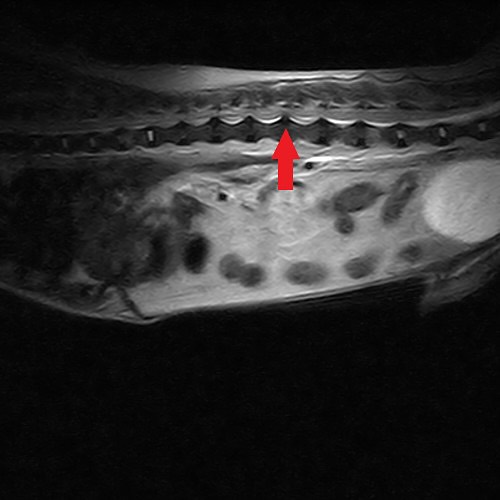

椎間板ヘルニアで手術を行ったワンちゃんです。MRIで椎間板ヘルニアと確定診断を行い、手術を行いました..

椎間板ヘルニアで手術を行ったワンちゃんです。MRIで椎間板ヘルニアと確定診断を行い、手術を行いました。手術前は歩くことができないですが、術後から3日くらいで歩けるようになりました。当院の手術は、全て手..